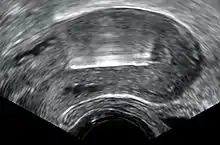

Transvaginal ultrasonography showing a perforated copper IUD as a hyperechoic (rendered as bright) line at right, 3 centimeters away from the uterus at left. The IUD is surrounded by a hypoechoic (dark) foreign-body granuloma.

Perforation: Very rarely, the IUD can move through the wall of the uterus.[20] Risk of perforation is mostly determined by the skill of the practitioner performing the insertion. For experienced medical practitioners, the risk of perforation is 1 per 1,000 insertions or less.[25]

Transvaginal ultrasonography visualizing an IUD with copper in the optimal location within the uterus.